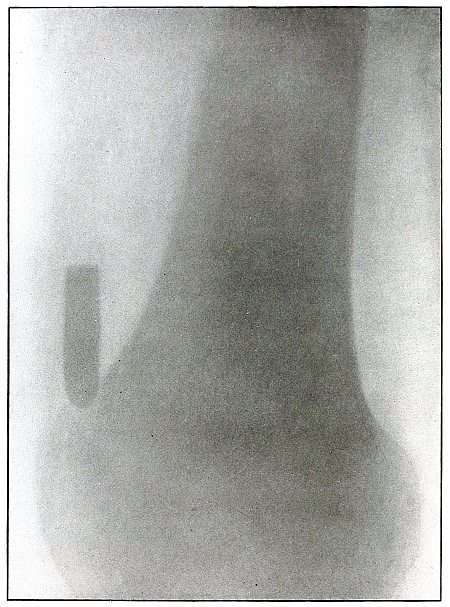

Gunshot fracture, ankle |

154 |